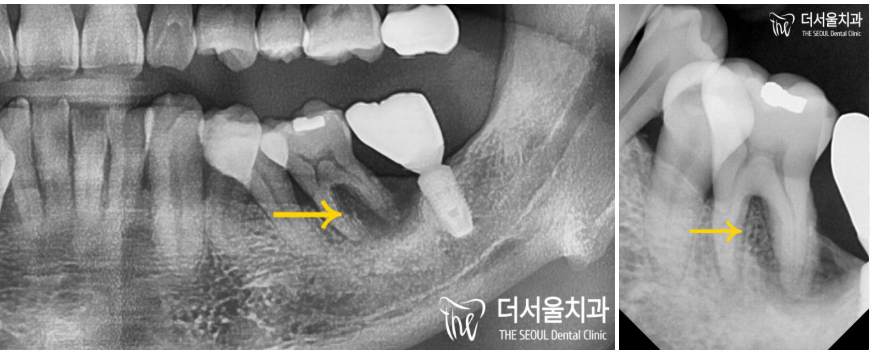

이분의 구강을 살펴보면

부정교합이 심한 것을 확인할 수 있는데요.

컴퓨터분석임플란트 를 심기 전,

내부 조직과의 위치 관계를 확인해야겠죠?

하악은? 하치조신경관~

초록색 선이 신경관의 위치입니다.

어? 그런데 제가 잘못봤나요..

신경관이 앞에 떡하니…

이럴 땐 더더욱 컴퓨터분석임플란트 를 해야 됩니다.